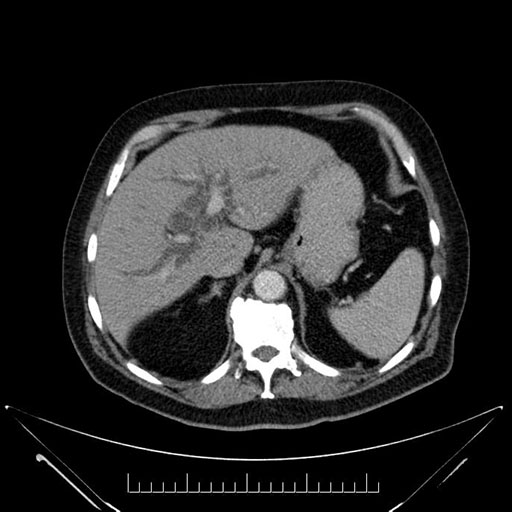

Axial - 3 months prior